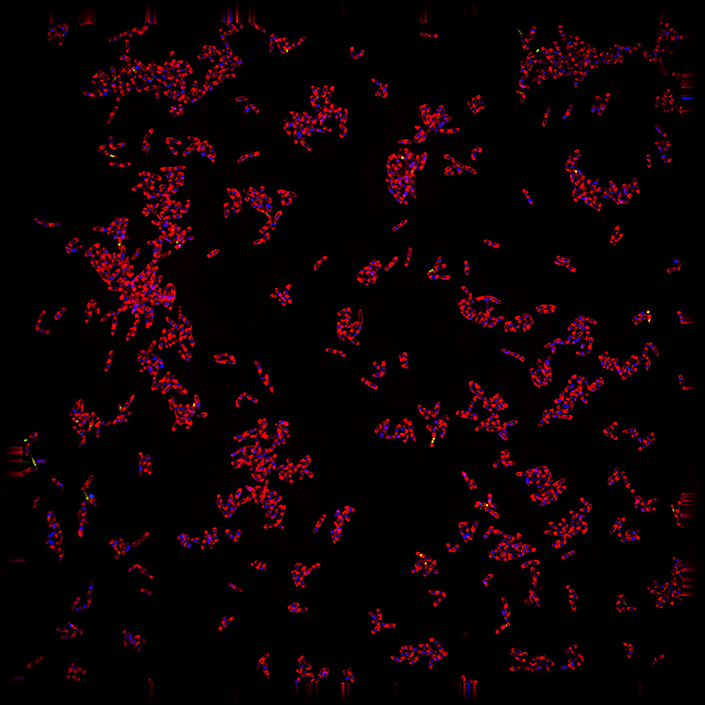

The creation of “MycoBCP,” a next-generation technology funded by the Gates Foundation, is detailed in the recent PNAS research. In order to overcome conventional obstacles and provide fresh perspectives on Mycobacterium tuberculosis cells, the novel approach combines BCP with deep learning, a form of artificial intelligence that makes use of neural networks that resemble brains.

Tuberculosis images are inherently difficult to interpret by the human eye and traditional lab measurements. Machine learning is much more sensitive in being able to pick up the differences in shapes and patterns that are important for revealing underlying mechanisms.

The MycoBCP technology was developed over two years by study lead authors Joseph Sugie and Diana Quach, who trained AI tools called convolutional neural networks using over 46,000 images of TB cells. Both Sugie and Quach are currently at Linnaeus Bioscience, and they both received PhDs from the Shu Chien-Gene Lay Department of Bioengineering and finished postdoctoral appointments in the Department of Molecular Biology’s Pogliano labs.